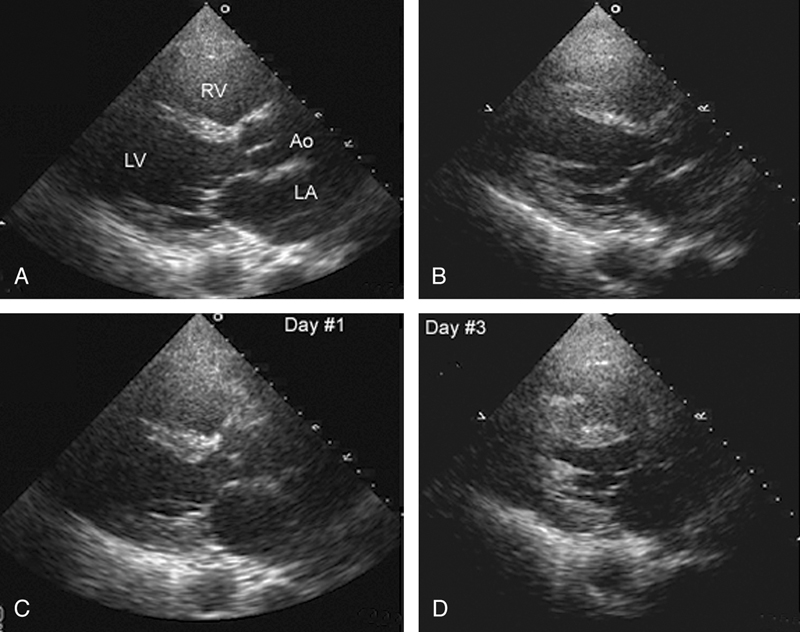

فحوصات تشخيصية لبعض امراض القلب والشرايين التاجية